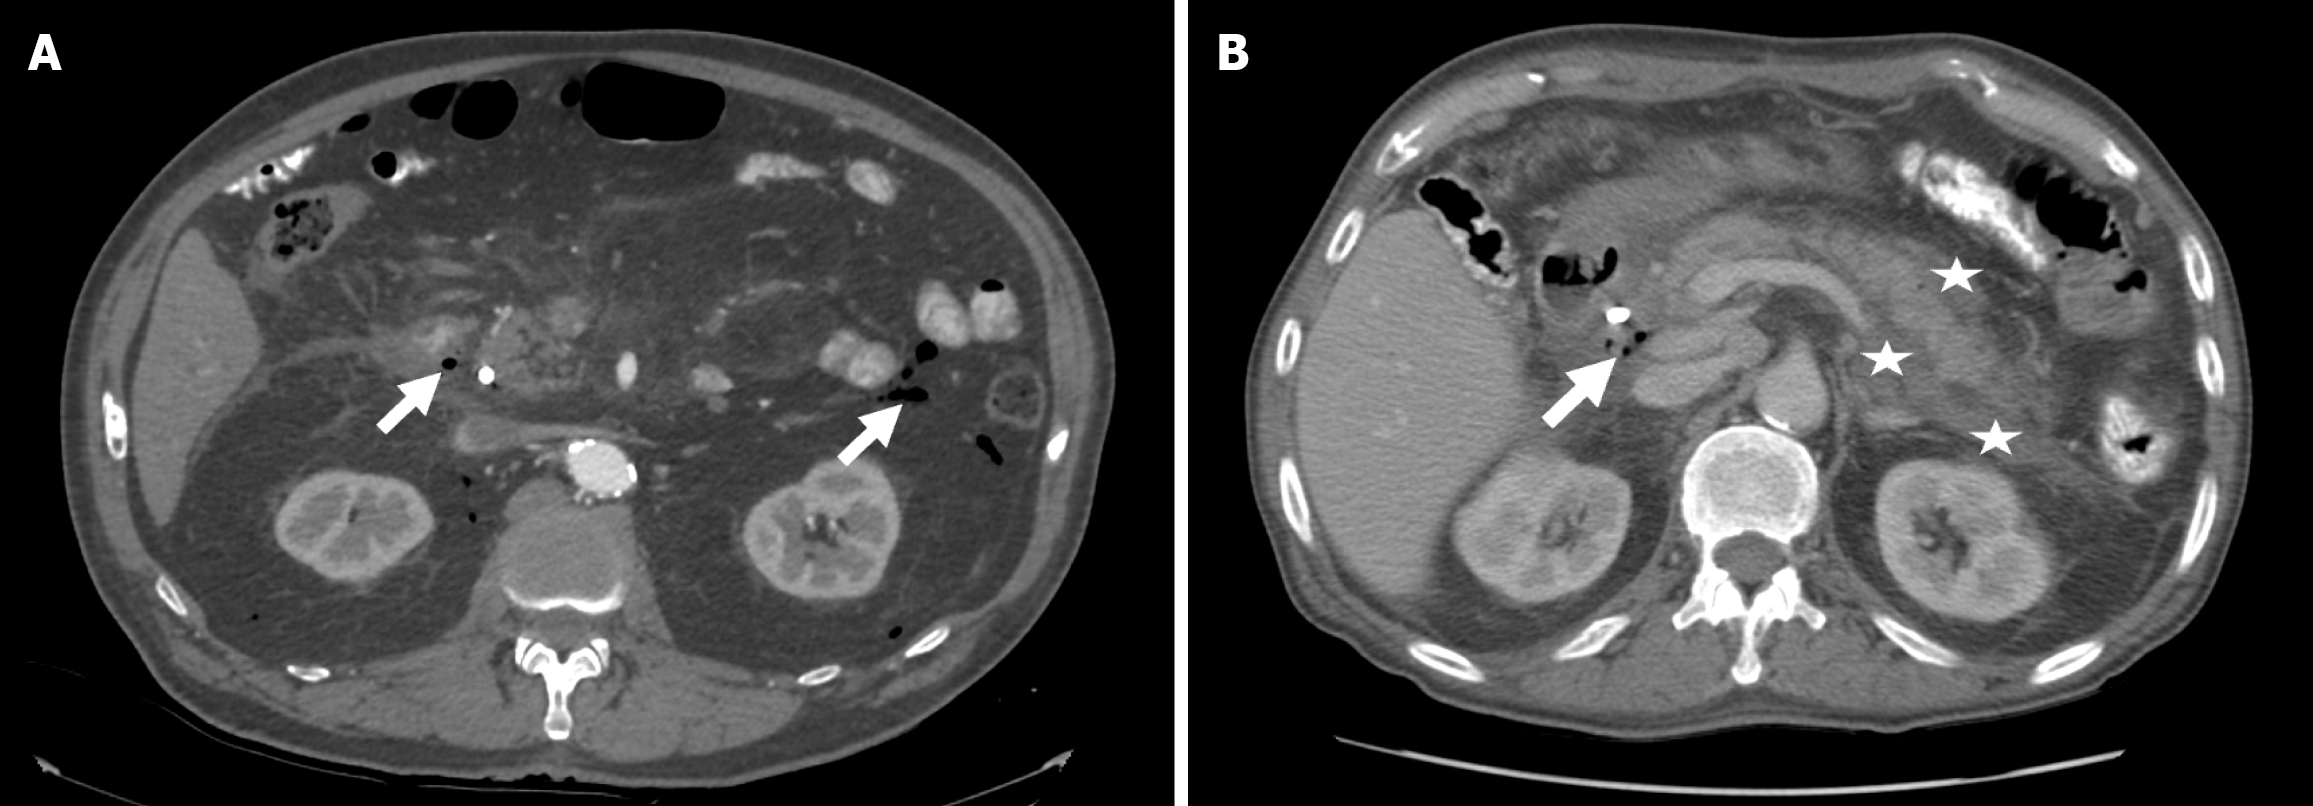

The patient was admitted to ICU for observation and conservative management. One day after the procedure a contrast-enhanced CT showed minor amount of free air in the retroperitoneal space with no further complications (Figure 2A). 3 days after the initial procedure the patient underwent a second look ERCP that showed adequate closure of the perforation and an enteral tube below the perforation was placed for enteral nutrition.

Two days after the procedure a contrast-enhanced CT was performed that showed malignant hilar infiltration, intrahepatic cholestasis, and perihilar free fluid and air (Figure 2B).